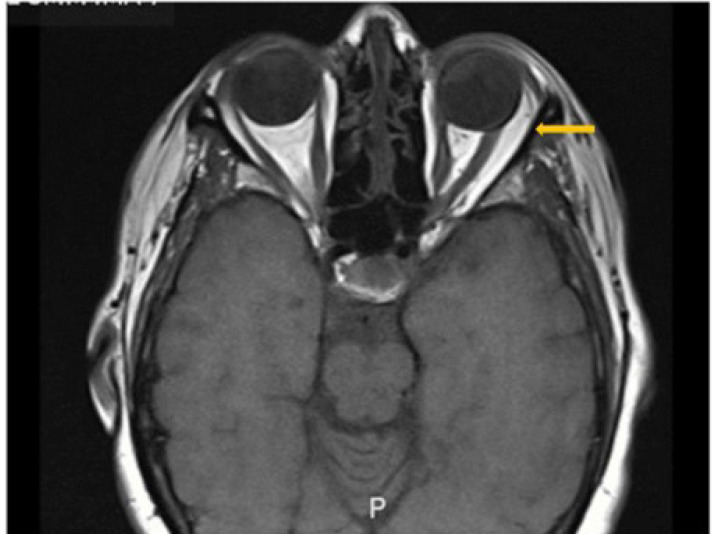

Case presentation: A 59-year-old woman with a history of traumatic sixth nerve palsy had previously undergone horizontal muscle strabismus surgeries. Following multiple left medial rectus recessions, lateral rectus resection, and BTA injections, esotropia persisted. The worsening of her condition led to emotional distress and impaired social interaction. Initial examination revealed marked esotropia and limited left eye abduction. Magnetic resonance imaging (SIGNA MR750w, GE Healthcare, Waukesha, WI, USA) of the left eye revealed a contracted medial rectus muscle and substantial atrophy of the left lateral rectus muscle. A modified Nishida procedure was performed with an injection of 3 units of BTA into the ipsilateral medial rectus muscle, resulting in improved ocular alignment and stable findings after nine postoperative months. Furthermore, we supported our successful outcome with a summary of similar reported cases of sixth nerve palsy managed using the modified Nishida procedure with or without adjunctive procedures.